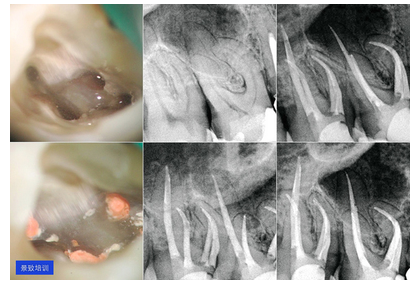

根管治疗是牙髓病和根尖周病的较常用的有效治疗方法。根管治疗术的原理是通过机械和化学方法去除根管内的大部分感染物,并通过充填根管、封闭冠部,防止发生根尖周病变或促进已经发生的根尖周病变的愈合。

根管治疗是一种较为复杂的牙髓治疗方法,使用的器械多,步骤多,需要经过多个治疗步骤和拍摄多张X光片才能完成整个过程。